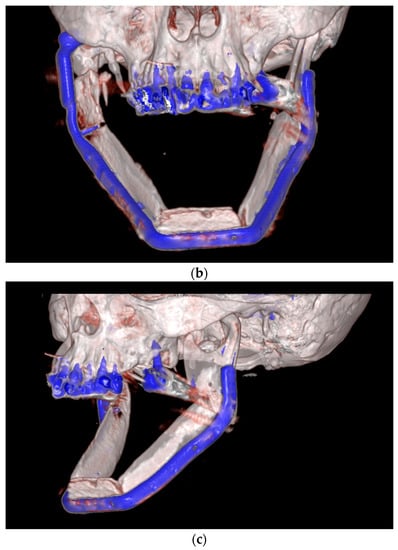

| September 2022: | Partial mandibular resection from the left mandibular angle to the right mandible, including the right temporomandibular joint, CAD/CAM-guided reconstruction with a bilateral free scapula flap with skin island, and patient-specific plate. In the course: